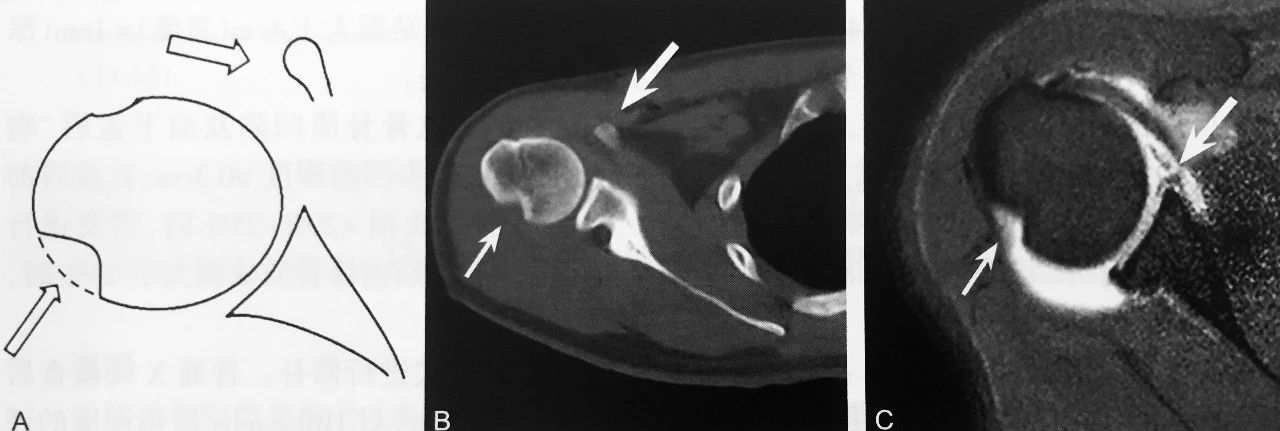

H i ll —Sachs 损伤

Hill-Sachs 损伤:A 图为模式图,骨折凹陷缺损区(细箭头),喙突(粗箭头);B 图右肩关节 CT 示肱骨头后外上骨折凹陷区(细箭头),喙突(粗箭头);C 图同一患者右肩 MRI 关节造影示肱骨头后外上骨折凹陷(细箭头),并盂唇损伤(粗箭头)

判读要点:

1、肩关节前下脱位的间接征象;

2、Hill-Sachs 损伤平面位于喙突水平;

3、CT 检查可对 Hill-Sachs 损伤程度进行评估;

4、MRI 对轻度急性期 Hill-Sachs 损伤具有较高的诊出率;

5、不同程度 Hill-Sachs 损伤,手术处理方式不一样。